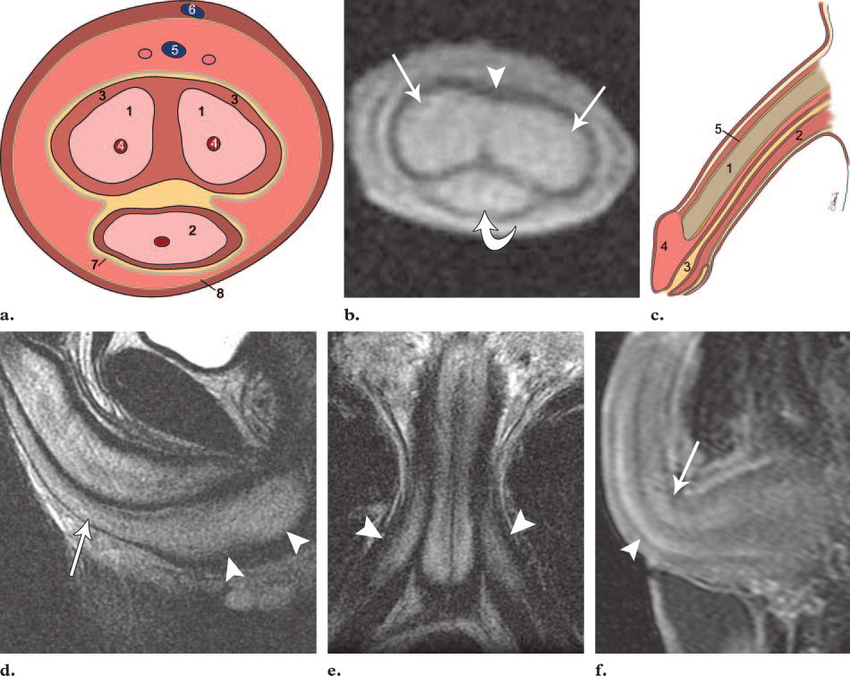

Phương pháp chụp cộng hưởng từ không sử dụng thuốc đối quang hiển thị rõ các cấu trúc giải phẫu của vùng bẹn, bìu, dương vật. Ngoài ra, có thể phát hiện được tổn thương ở các khu vực này nếu có.

Chụp cộng hưởng từ bìu, dương vật có tiêm thuốc cản từ ngoài mục đích khảo sát hình thái và tổn thương còn nhằm đánh giá tình trạng tưới máu của các cấu trúc, tổn thương của cơ quan sinh dục ngoài của nam giới.

Cũng giống như chụp cộng hưởng từ không sử dụng đối quang, hình ảnh chụp bằng phương pháp hiển thị rõ các cấu trúc giải phẫu của vùng bẹn, bìu, dương vật, đồng thời phát hiện được các tổn thương nếu có và đặc điểm ngấm thuốc đối quang từ.